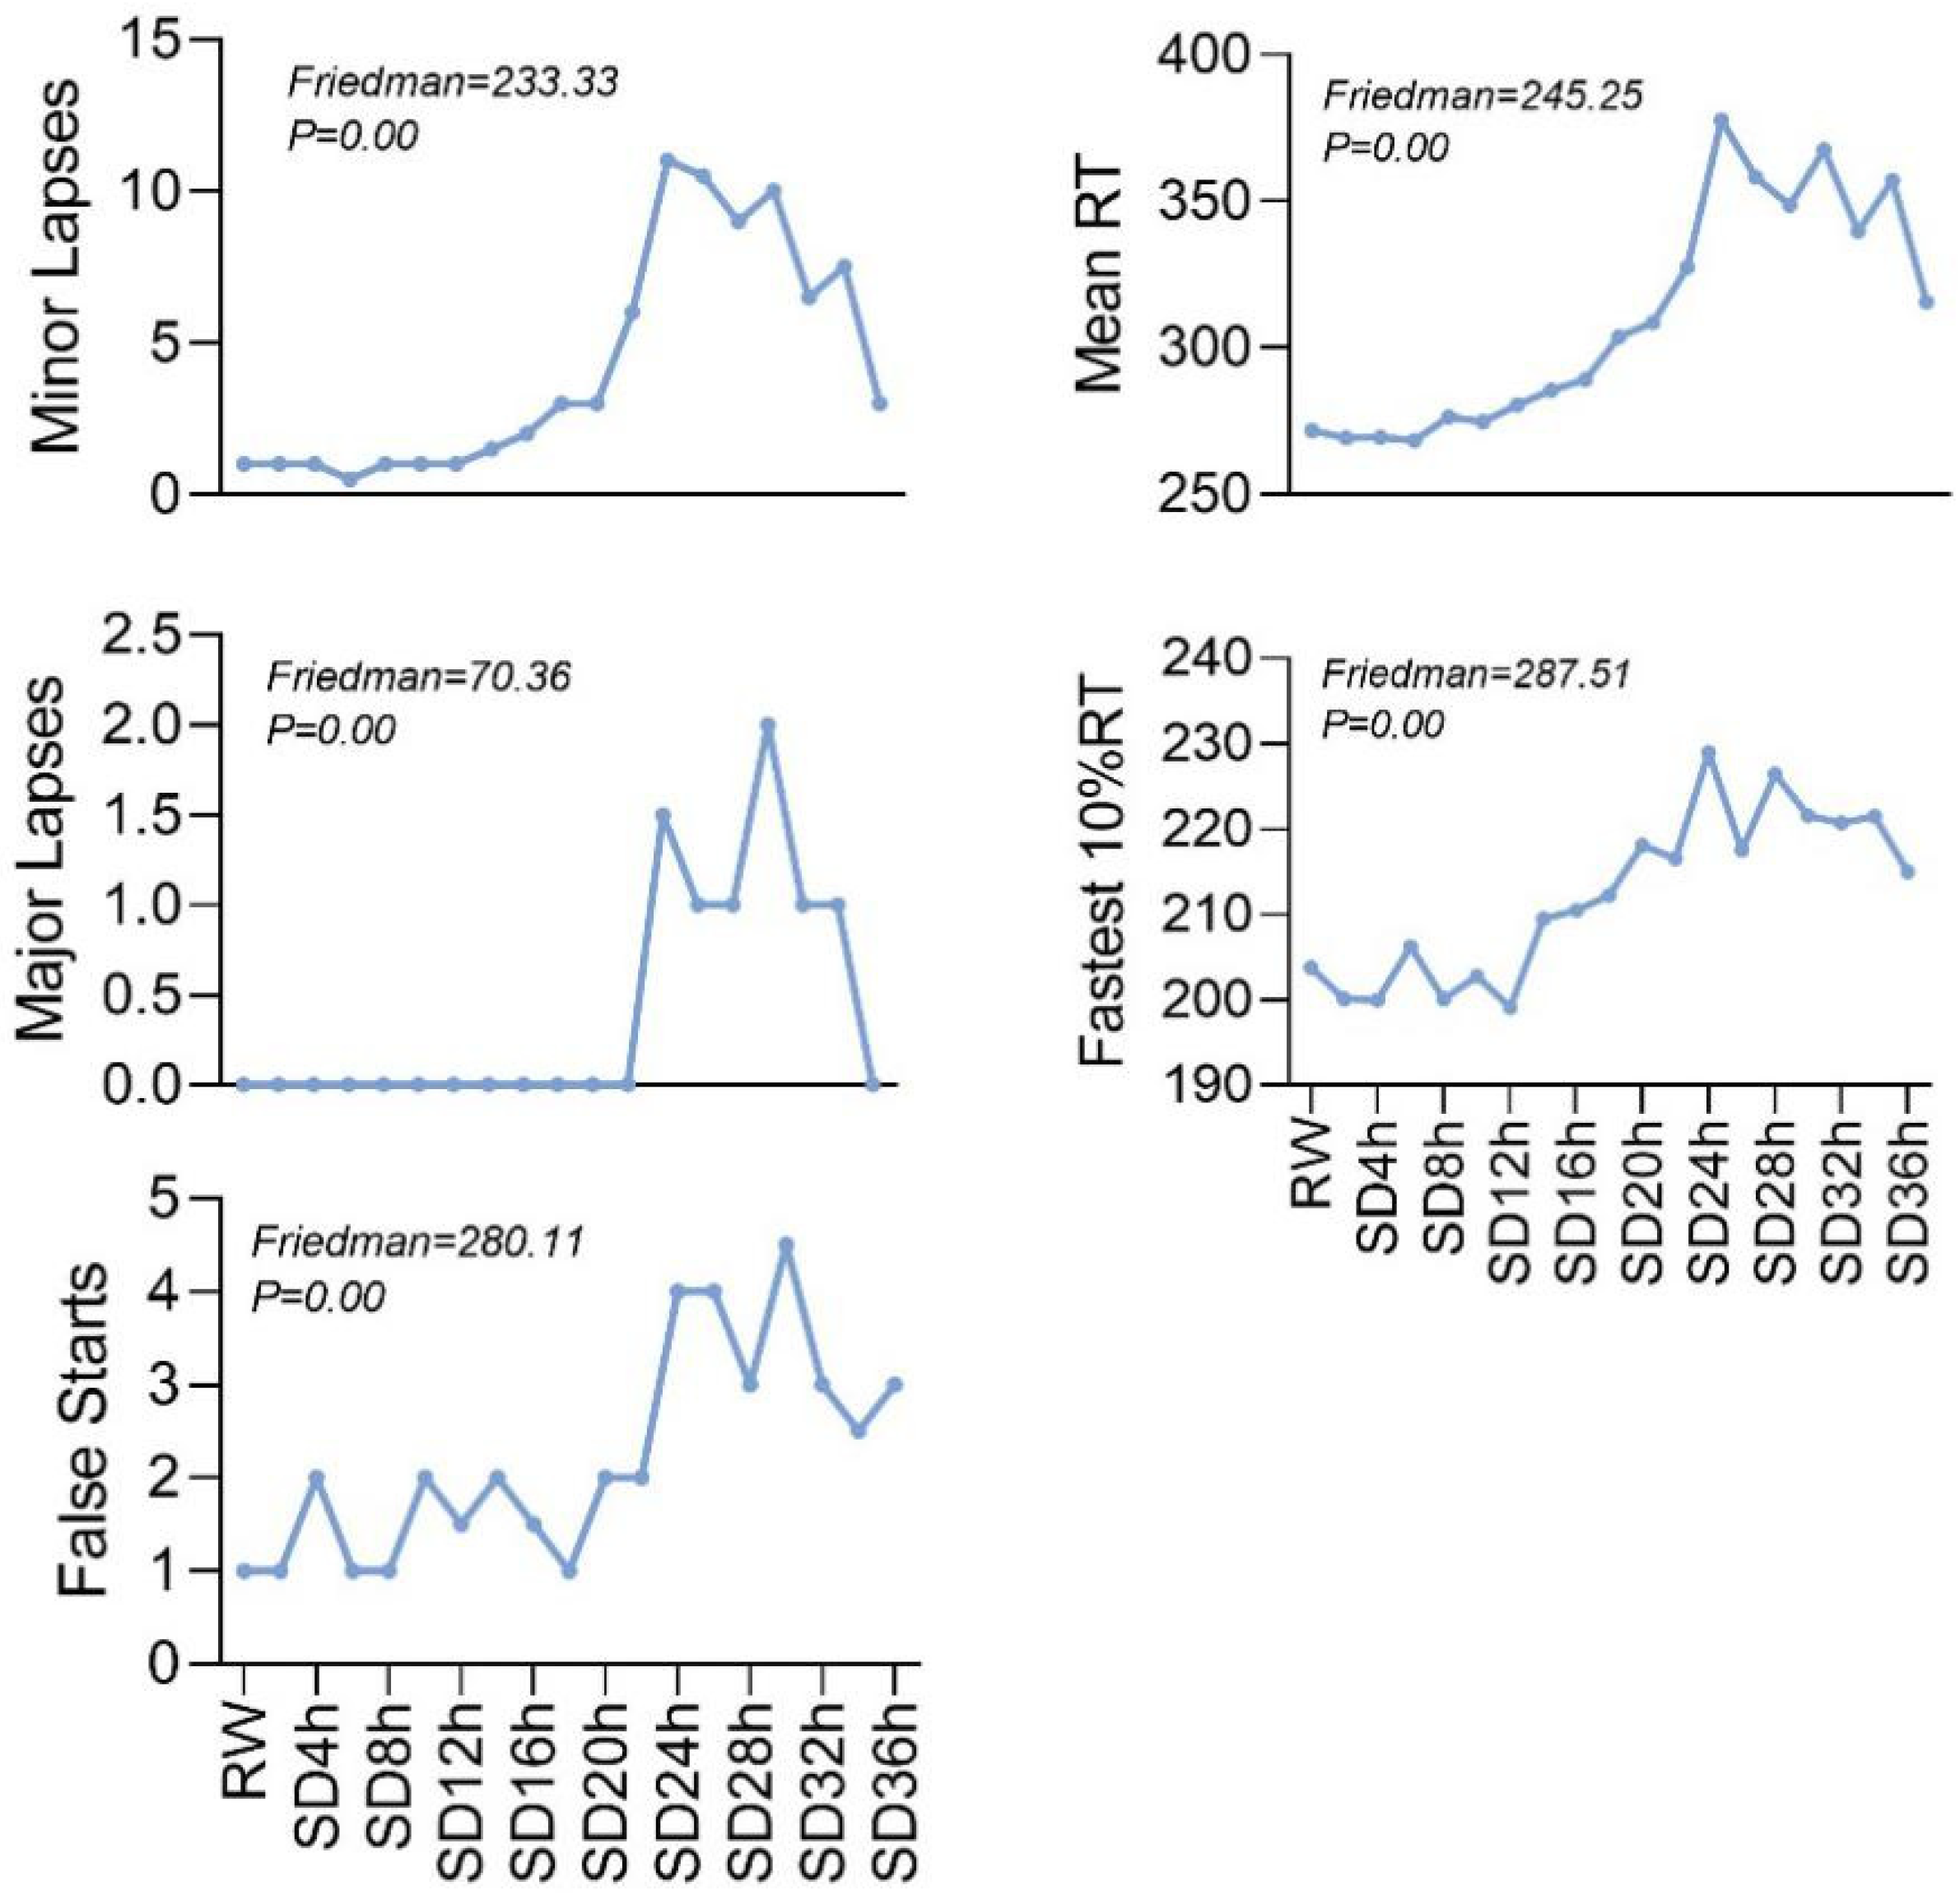

3.1. PVT Change Performance

| Periods | Minor Lapses | Major Lapses | False Starts | Mean RT | Fastest 10% RT |

|---|---|---|---|---|---|

| RW | 1 (0, 2) | 0 (0, 1) | 1 (0, 3) | 271.77 (243.29, 286.73) | 203.75 (187.75, 217.42) |

| SD2h | 1 (0, 2) | 0 (0, 0) | 1 (0, 3) | 269.14 (248.20, 289.85) | 200.06 (179.40, 211.73) |

| SD4h | 1 (0, 2) | 0 (0, 0) | 2 (0, 3) | 269.43 (257.78, 285.34) | 199.94 (183.78, 211.90) |

| SD6h | 0.5 (0, 2) | 0 (0, 0) | 1 (0, 3) | 268.27 (255.67, 298.42) | 206.21 (192.60, 214.10) |

| SD8h | 1 (0, 2) | 0 (0, 0) | 1 (0, 4) | 276.34 (257.18, 296.77) | 200.09 (192.90, 217.70) |

| SD10h | 1 (0, 3) | 0 (0, 0) | 2 (0, 6) | 274.60 (264.77, 298.31) | 202.77 (183.67, 209.67) |

| SD12h | 1 (0, 2) | 0 (0, 0) | 1.5 (0, 4) | 280.30 (262.20, 296.73) | 199.11 (191.30, 218.00) |

| SD14h | 1.5 (1, 3) | 0 (0, 0) | 2 (1, 3) | 285.50 (261.49, 312.90) | 209.47 (200.33, 222.60) |

| SD16h | 2 (1, 4) | 0 (0, 0) | 1.5 (0, 3) | 289.02 (269.29, 320.59) | 210.45 (195.78, 227.70) |

| SD18h | 3 (1, 7) | 0 (0, 1) | 1 (0, 3) | 303.61 (277.70, 346.80) | 212.20 (202.33, 231.33) |

| SD20h | 3 (1, 6) | 0 (0, 1) | 2 (0, 4) | 308.67 (288.99, 328.13) | 218.06 (206.70, 224.36) |

| SD22h | 6 (2, 8) | 0 (0, 1) | 2 (0, 4) | 327.42 (301.67, 359.56) | 216.55 (204.90, 236.90) |

| SD24h | 11 (5, 16) | 1.5 (0, 3) | 4 (1, 6) | 377.71 (320.55, 438.73) | 228.96 (218.44, 237.50) |

| SD26h | 10.5 (4, 18) | 1 (0, 5) | 4 (1, 7) | 358.15 (326.30, 468.54) | 217.54 (210.67, 229.13) |

| SD28h | 9 (2, 13) | 1 (0, 4) | 3 (1, 7) | 348.57 (298.82, 413.51) | 226.41 (205.90, 241.40) |

| SD30h | 10 (5, 15) | 2 (0, 5) | 4.5 (2, 8) | 367.55 (331.16, 420.60) | 221.50 (203.50, 232.78) |

| SD32h | 6.5 (4, 16) | 1 (0, 4) | 3 (1, 5) | 339.68 (310.89, 423.39) | 220.72 (205.44, 231.40) |

| SD34h | 7.5 (5, 12) | 1 (0, 3) | 2.5 (1, 6) | 357.11 (312.21, 397.39) | 221.43 (207.00, 233.33) |

| SD36h | 3 (1, 10) | 0 (0, 2) | 3 (1, 5) | 315.53 (286.93, 359.24) | 214.93 (201.20, 225.20) |

| Friedman | 233.33 | 70.36 | 280.11 | 245.25 | 287.51 |

| P | 0.00 | 0.00 | 0.00 | 0.00 | 0.00 |